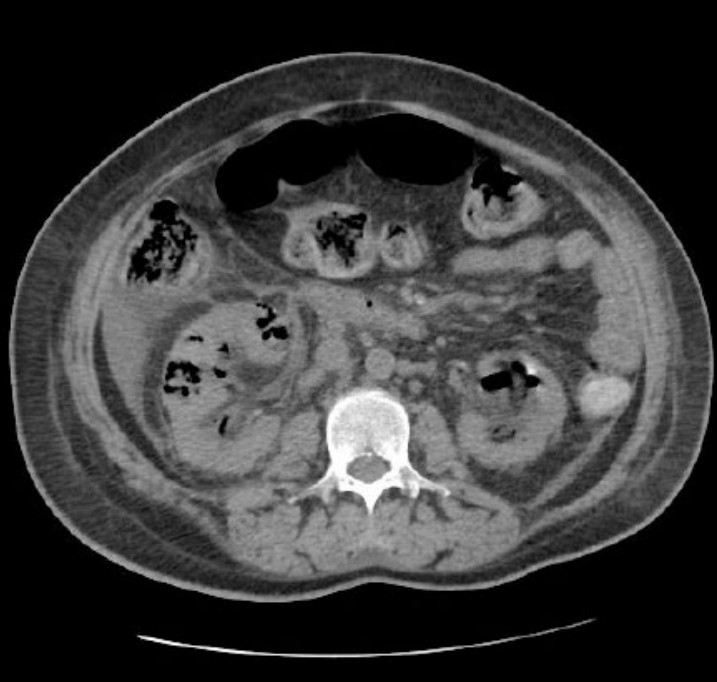

A 45 year old diabetic patient presents with 2 days of bilateral flank pain and fever. Tem 38 <ul><li>HR 100</li><li>BP …